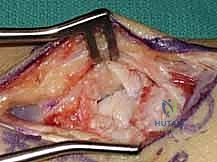

1. النهج الجراحي الأمامي (Volar Approach)

يُفضل البروفيسور هطيف في معظم حالات عدم الالتئام المصحوبة بتشوه محدب استخدام المدخل الأمامي (من جهة راحة اليد).

لماذا؟ لأن هذا النهج يحافظ على الإمداد الدموي الظهري المتبقي (والذي ذكرنا أنه يمثل 70% من تغذية العظم)، كما أنه يوفر رؤية ممتازة للكسر، ويسهل عملية تصحيح التشوه المحدب بفتح زاوية العظم من الأمام.

2. تنظيف موقع عدم الالتئام (Debridement)

بمجرد الوصول إلى العظم الزورقي، يقوم الجراح بإزالة النسيج الليفي المتكون بين شظايا العظم. ثم يتم استخدام أدوات دقيقة (Curettes or high-speed burrs) لكشط وحفر حواف العظم المتصلبة والميتة حتى يتم الوصول إلى عظم إسفنجي صحي ينزف دماً. هذه العلامة تُعرف طبياً بـ "علامة البابريكا" (Paprika Sign)، وهي مؤشر حاسم على أن العظم المتبقي حي وقادر على الالتئام.